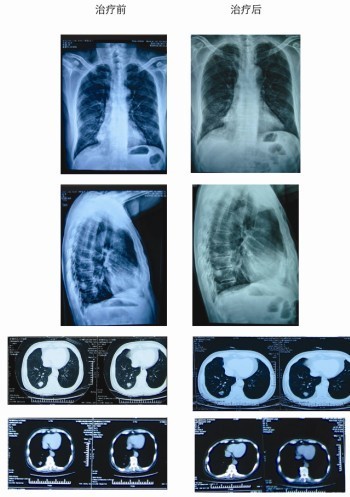

由于余某的病情比较严重,根据专家的建议,余某在医院接受了两个疗程的治疗。4月初,余某病情稳定,肺部肿瘤回缩达21.8%,转移的癌细胞被全部清除。